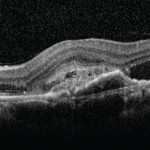

Diagnosi di RAP (retinal angiomatous proliferation): un approccio multi-imaging